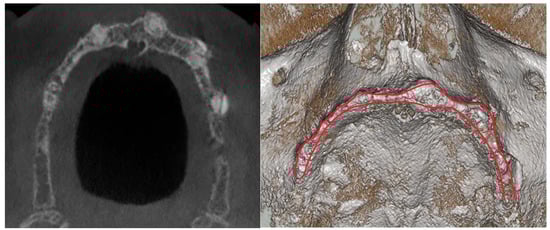

3.3. Hard Tissues Gain

3.4. Soft Tissue Management